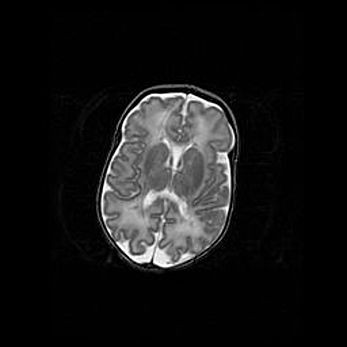

Сообщающаяся гидроцефалия. Кистозная энцефаломаляция головного мозга.

Возраст: 3 месяца 4 дня

Вес: 3100 г

Пол: женский

Окружность головы: 34 см

Срок гестации: 31 неделя

Кистозная энцефаломаляция головного мозга - одна из форм поражения головного мозга в детском возрасте. Характеризуется возникновением множественных и распространённых кист в коре, белом веществе и подкорковых образованиях головного мозга у плодов, новорождённых и детей раннего возраста. Развитие кистозной энцефаломаляции связано с внутриутробной асфиксией и гипотонией, родовой травмой, тромбозом синусов, пороками развития сосудов, инфекциями, сепсисом и другими причинами. Наиболее значимые инфекционные агенты: вирусы простого герпеса, цитомегалии, краснухи, токсоплазмы, энтеробактерии, золотистый стафилококк и другие.